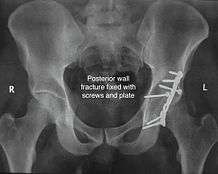

Posterior wall fracture

This is the most common variety of fracture

Cause: Occurs due to dash board injury. When a person travelling in a vehicle involved in head-on collision, the force applied over the flexed knee travels along the femur bone to the head of femur breaking the posterior wall of the acetabulum. The head of the femur is dislocated outside the joint.

Associated injury: The broken bone pieces or the dislocated head of the femur may injure the important Sciatic nerve causing paralysis of the foot; this may or may not recover depending on the extent of injury to the nerve.

The posterior wall fragment may be one large piece, or multiple pieces, and may be associated with impaction of the bone

How to diagnose: Best seen in obturator oblique view

CT scan helps in identifying impaction of bone pieces and if there are pieces in the joint

MRI may be done to identify the extent of injury to the sciatic nerve

Treatment: if the femur head is dislocated, it should be reduced as soon as possible, to prevent damage to its blood supply. This is preferably done under anaesthesia, following which, leg is kept pulled by applying traction to prevent joint from dislocating.

The final management depends on the size of the fragment(s), stability and congruence of the joint.

In some cases traction for six to eight weeks may be the only treatment required

If the fragments do not fall into place, or if there are bone pieces in the joint, or if the joint is unstable, surgical fixation using screw(s) and plate(s) is performed

Post-surgery treatment: depending on the stability achieved, the person may be allowed standing and walking with help of support for about six to eight weeks.

Full function may return in about three months.

Complications: Sciatic nerve injury and stoppage of blood supply to femoral head at the time of accident or during surgery may occur. Deep vein thrombosis and pulmonary embolism are other complications that may occur in any type of injury to the acetabulum.